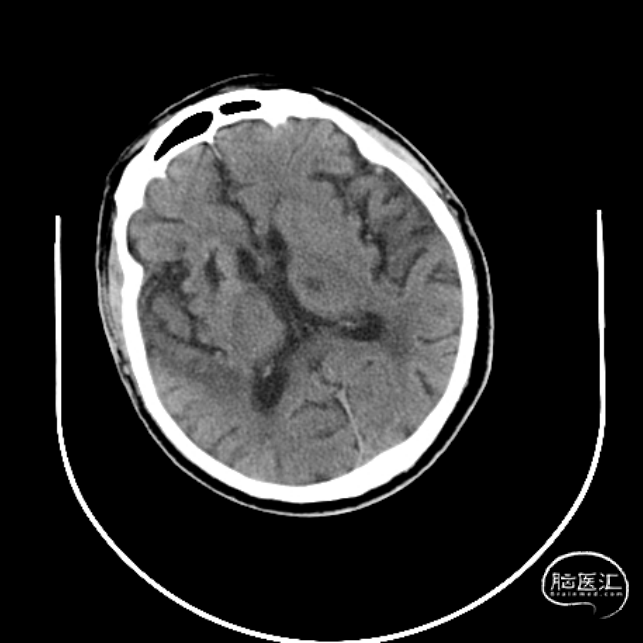

术后24小时CT示

术后24小时查体:神清,言语欠清,双侧瞳孔等大正圆,直径3.0mm。直接间接对光反射灵敏,双眼各向活动正常,右侧鼻唇沟浅,伸舌右偏,左侧肢体肌力5级,右侧上肢3级,下肢肌力4级,右侧巴氏征阳性。急诊NIHSS评分:5分。